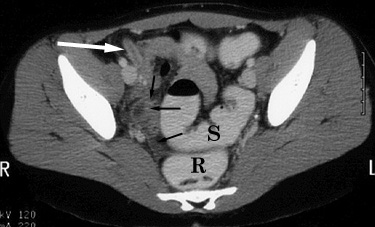

CT. A. The left-hand image below was obtained without intravenous, oral or rectal contrast administration. It demonstrates an inflamed appendix (arrow). Note fluid in the right adnexa and cul-de-sac regions (*). Differentiation between fluid-filled bowel loops, free fluid, and abscess is difficult. B. The right-hand image below was obtained after administration of intravenous and rectal contrast. Differentiation of the rectosigmoid colon (R, S) from abnormal fluid collections is facilitated. Abnormal fluid is identified in the right pelvis (black arrows). The inflamed appendix with enhancing walls (white arrows) is also better delineated. |